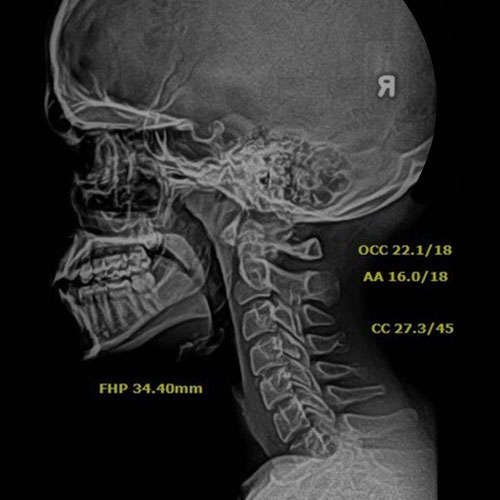

After Corrective Chiropractic Care: Following a customized course of corrective chiropractic treatment, repeat X-rays demonstrated measurable improvement in cervical alignment. More importantly, those structural changes translated into real-life results — reduced pain, improved function, and a return to daily activities with confidence.

This is the difference between symptom-based care and corrective care.

Why Before & After X-Rays Matter:

• X-rays allow us to move beyond guesswork and provide objective proof of progress. They help us:

• Identify loss of cervical curvature and postural stress

• Design personalized treatment plans based on spinal structure

• Track measurable changes over time

• Confirm that care is correcting the problem — not just masking symptoms